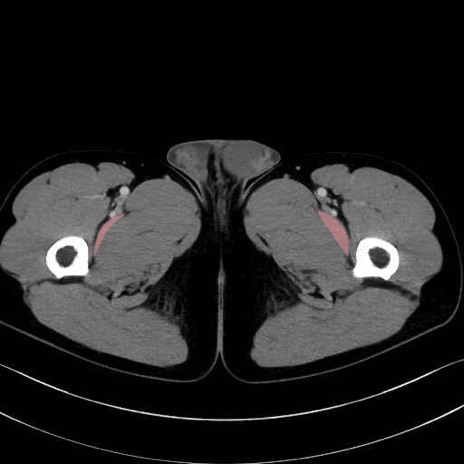

恥骨筋 (Pectineus)